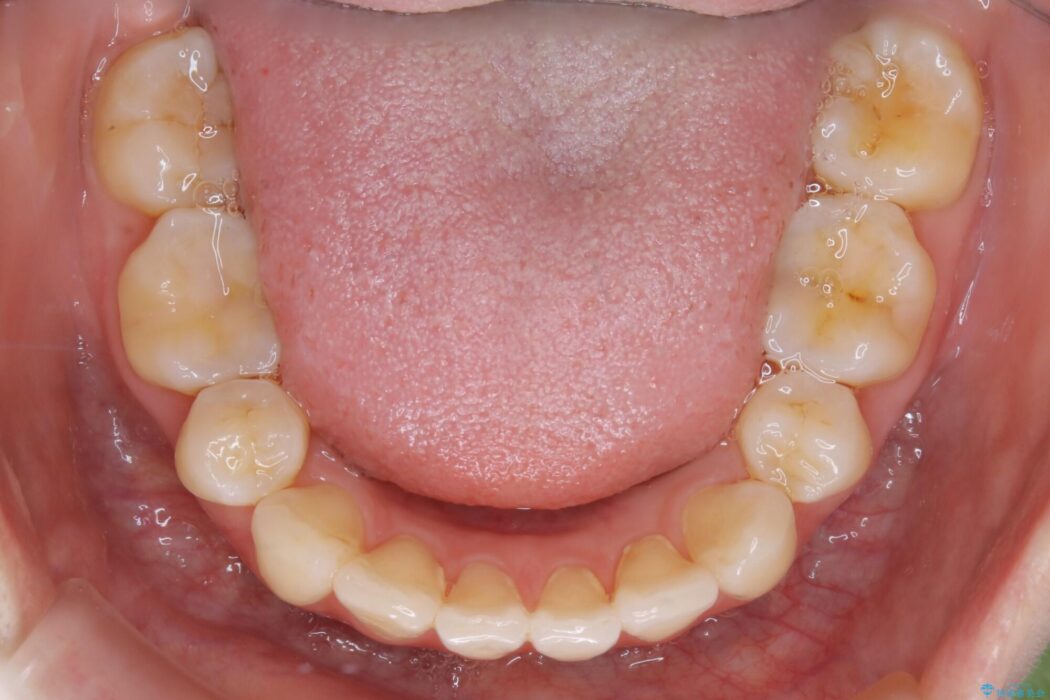

治療後について

後戻りしていた歯列もきれいに整い患者様にはご満足いただけました。

小学生~高校生の間に矯正治療をされている方で、その後の成長や生活の変化におけるリテーナー(後戻り防止装置)の継続使用が困難となり、叢生(ガタつき)が時間の経過で再発してしまうケースが多くあります。

一度目の矯正治療の際に抜歯をしていたり後戻りでのガタつきの度合いによって再矯正における治療期間が最初の矯正治療と同程度に要する場合もあります。